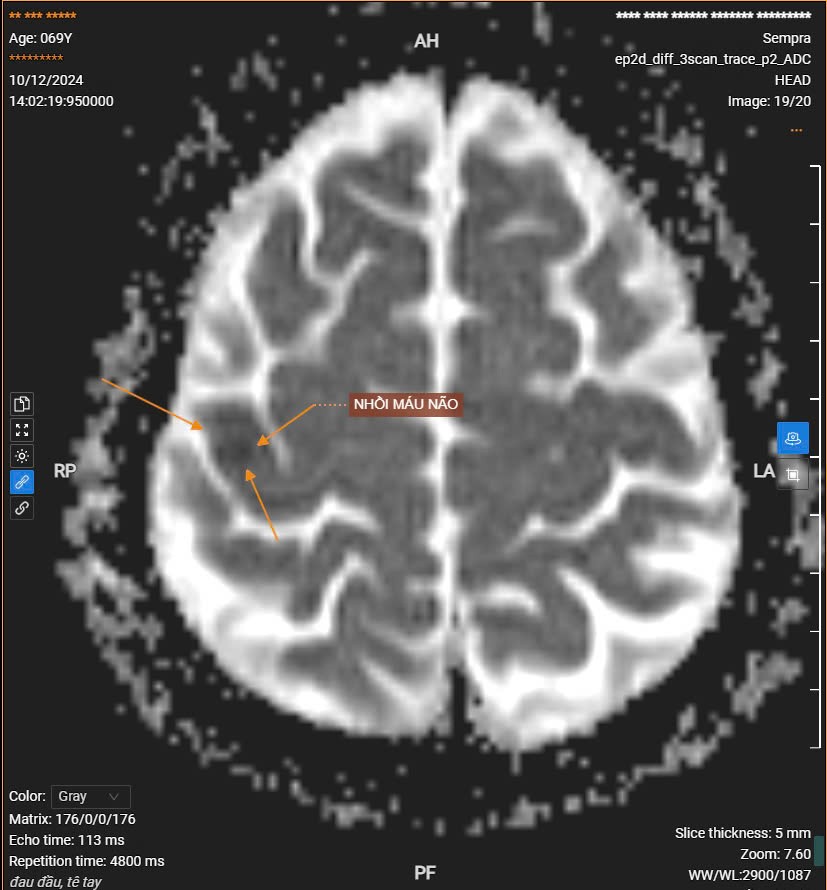

Ngày 13/12/2024 Bệnh viện Thái Bình đã tiếp nhận bệnh nhân B.T.T 71 tuổi, đến khám với triệu chứng, đau ngực, tăng huyết áp, đau đầu âm ỉ